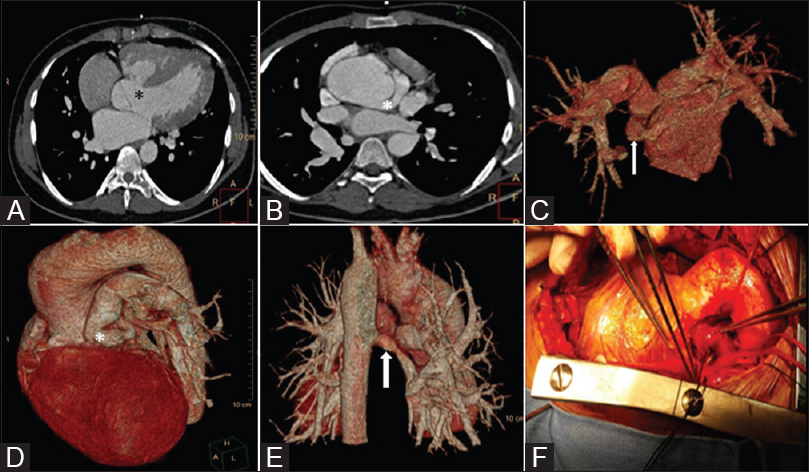

Pulmonary atresia and ventricular septal defect,Coronary artery as the primary source of pulmonary blood flow

Collateral or fistula? Coronary artery as the primary source of pulmonary blood flow in a patient with pulmonary atresia and ventricular septal defect p. 433

Anurag Yadav, Salil Bhargava, T B S Buxi, Krishna Sirvi

DOI:10.4103/ijri.IJRI_489_17

In patients with pulmonary atresia and ventricular septal defect (PA/VSD), a coronary artery being the primary source of pulmonary blood flow is a rare entity. We describe two cases of PA/VSD with coronary-to-pulmonary artery fistula with emphasis on the role of Computed Tomographic Angiography (CTA) in depicting all the sources of pulmonary blood supply, to predict surgical management and need for unifocalization of Major Aortopulmonary Collateral Arteries (MAPCA's).